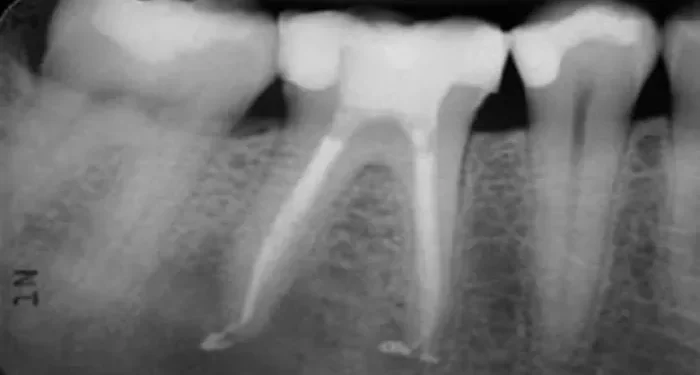

X – Rays?

X – rays are an essential tool for diagnosing the cause of the pain. They can show the dentist what’s going on inside the tooth and the surrounding bone. X – rays can reveal the presence of a crack in the root, an abscess at the root tip, or signs of bone loss due to periodontal disease. If there’s an abscess at the root tip, it will show up as a dark area on the X – ray. X – rays can also help the dentist see if the root canals were filled properly and if there are any signs of residual bacteria or infection.?